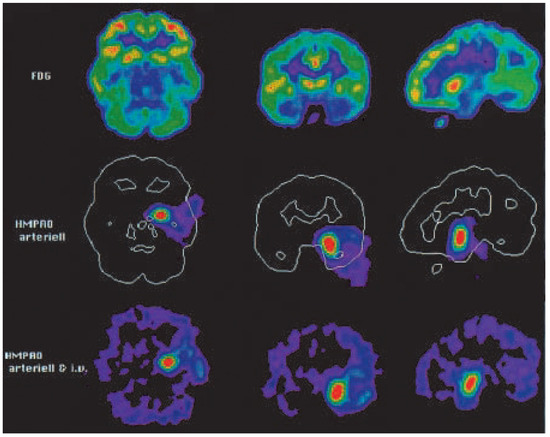

Die Bedeutung der Amobarbital-induzierten EEG-Veränderungen bei den verschiedenen Formen des selektiven Temporallappen-Amobarbital-Testes

The electroencephalographical changes observed in three different types of selective temporal lobe amobarbital tests were studied during 44 tests in 40 patients. A so-called balloon-occlusion test was performed 19 times, a selective catheterization of the anterior choroidal artery 20 times and a catheterization of the peduncular segment of the posterior cerebral artery 5 times. The EEG changes were monitored with intracranial electrodes and scalp-electrodes whenever possible or, when not, with scalp-electrodes only. A delta increase ipsilateral to the side of the injection was observed in the majority of tests. An increase in epileptiform activity is the second frequent pattern. Seldom an ipsilateral reduction of epileptiform activity or no change at all were observed. A clear ipsilateral delta increase, an increase in epileptiform activity and a decrease of epileptiform activity in the intracranial recordings are signs that the target structures are inactivated. A slight delta increase or no change at all do not indicate an inactivation. Only the combined monitoring with intracranial and scalp-electrodes together allows for a correct interpretation of the EEG changes. Full article

Figure 1